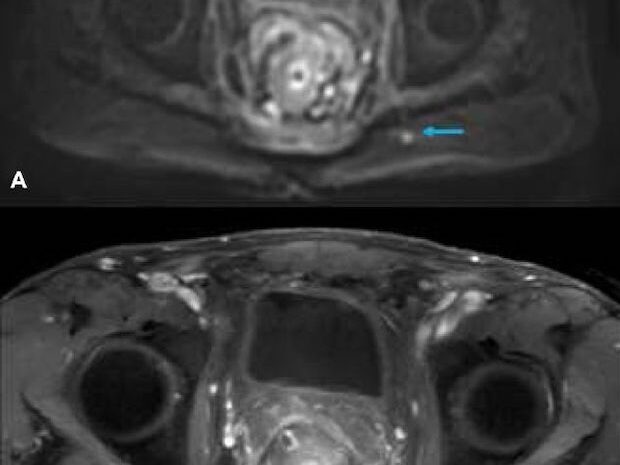

Colorectal cancer diagnostic imaging with 3T MRI enables early detection and precise evaluation of tumors for accurate diagnosis and treatment planning.